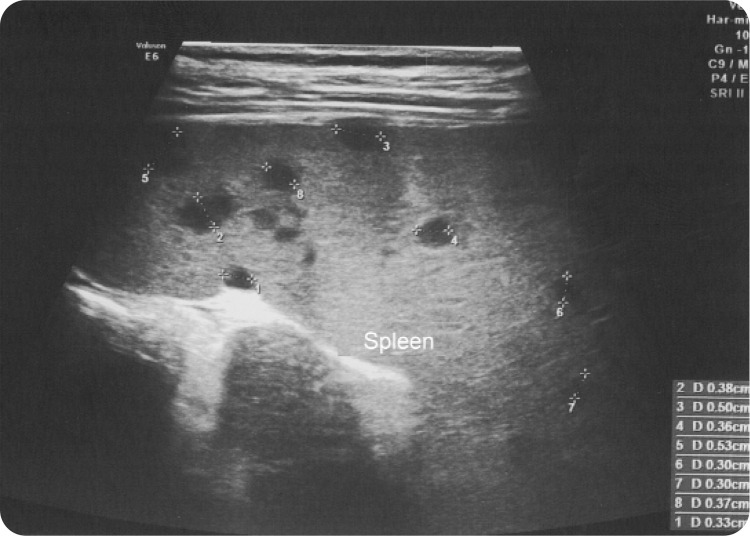

Results: We present the case of a 6-year-old girl with fever, abdominal pain, non-purulent bilateral conjunctivitis, maculopapular rash on the trunk, bilateral cervical lymphadenopathy, and oral mucosa erythema, meeting KD diagnostic criteria. Echocardiography revealed coronary artery dilatations. Despite initial intravenous immunoglobulin (IVIG) treatment eighteen hours later the general condition worsened, with the recurrence of fever, diffuse myalgia, severe abdominal pain, and vomiting. A detailed history revealed a cat scratch three weeks before onset, along with an erythematous nodule on the thumb, axillary lymphadenopathy, a typical hypoechoic splenic lesion in abdominal ultrasonography, and highly elevated IgM and IgG antibodies for Bartonella henselae titres, leading to a diagnosis of atypical CSD. Successful treatment involved a three-month course with erythromycin. Our literature review revealed five cases of co-occurring KD and CSD and six cases where CSD mimicked autoimmune diseases or malignancies.

Conclusion: The presented case illustrated the expanding spectrum of B. henselae infection and emphasised the importance of including it in the differential diagnosis of KD and prolonged fever syndromes. We suggest incorporating abdominal ultrasonography into the initial diagnostic workup, considering it to be essential before empiric therapy initiation.